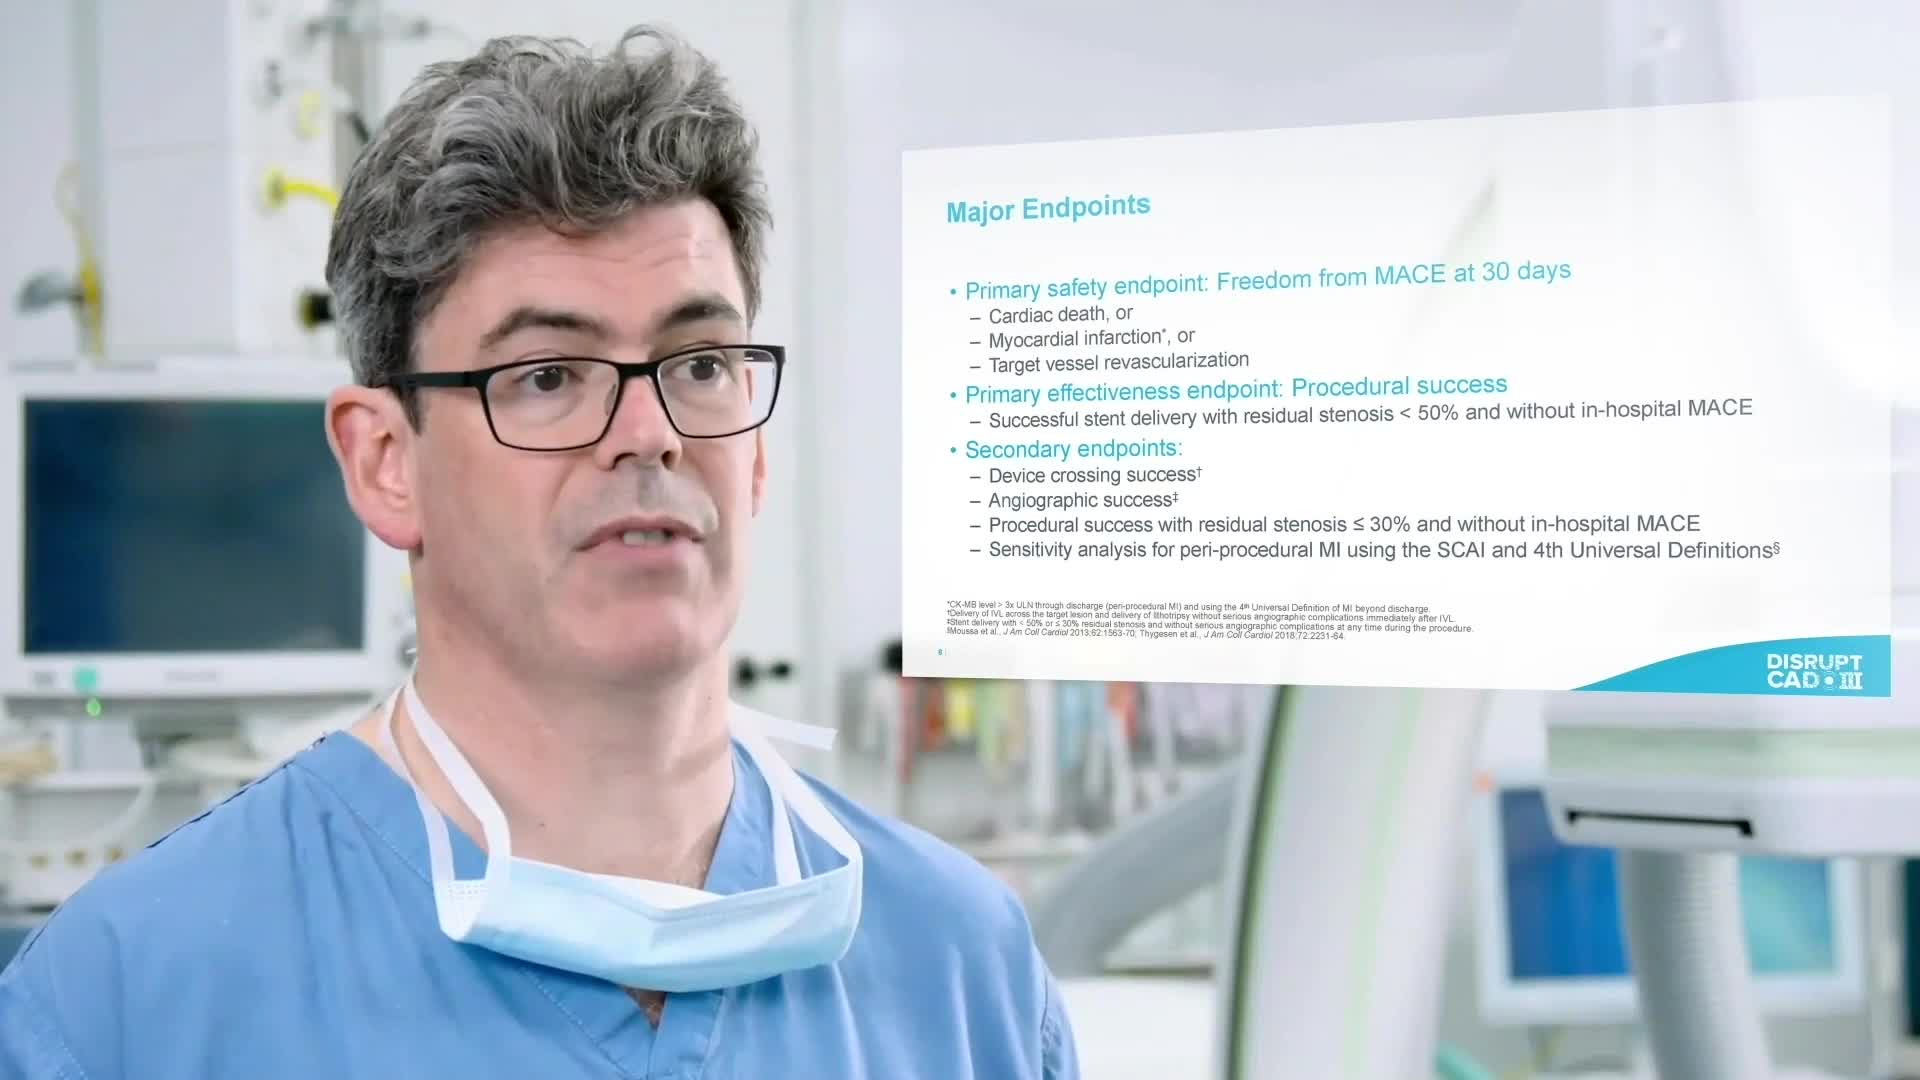

Intravascular Lithotripsy for Treatment of Severely Calcified Coronary Artery Disease: The Disrupt CAD III Study